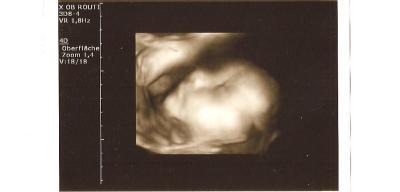

huhu ihr lieben, heut hatte ich das erste mal ctg schreiben, alles unauffällig, baby hat gut gestrampelt UND TATATATATATAAAAAA, er hat sich wieder in SL gedreht, juhu :)))))) freue mich sehr! hoffe, dass er jetzt auch so bleibt, der arzt meinte, ab einem gewissen zeitpunkt drehen sie sich nur noch gaaanz selten :) das bildchen ist vom 07.06. heut gabs keins, erst in 2 wochen wieder! habe weiterhin 7kg zugenommen, blutdruck 110/65 (wie immer) und mein hb ist durch die Ferro Sanol von 10,6 auf 12,2 gestiegen, wieder etwas positives (nehme sie seit einer woche und 6 tagen)!!!! juhuuuu! euch einen schönen tag!!!! liebe grüße von einer glücklichen marta die ab heute in der 33 ssw ist :)))

Bild zu Heute VU mit Bildchen :))) - Forum für August - Mamis

das klingt doch alles ganz super. Und das Bildchen ist ja soooo süß und richtig detailliert. Hui, ich freue mich auch schon sooooo sehr auf unsere Maus. LG sonnenschein11